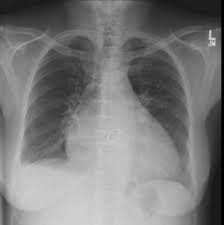

Chest X Ray Showing Moderate Cardiomegaly And Prominent Bibasilar Download Scientific Diagram